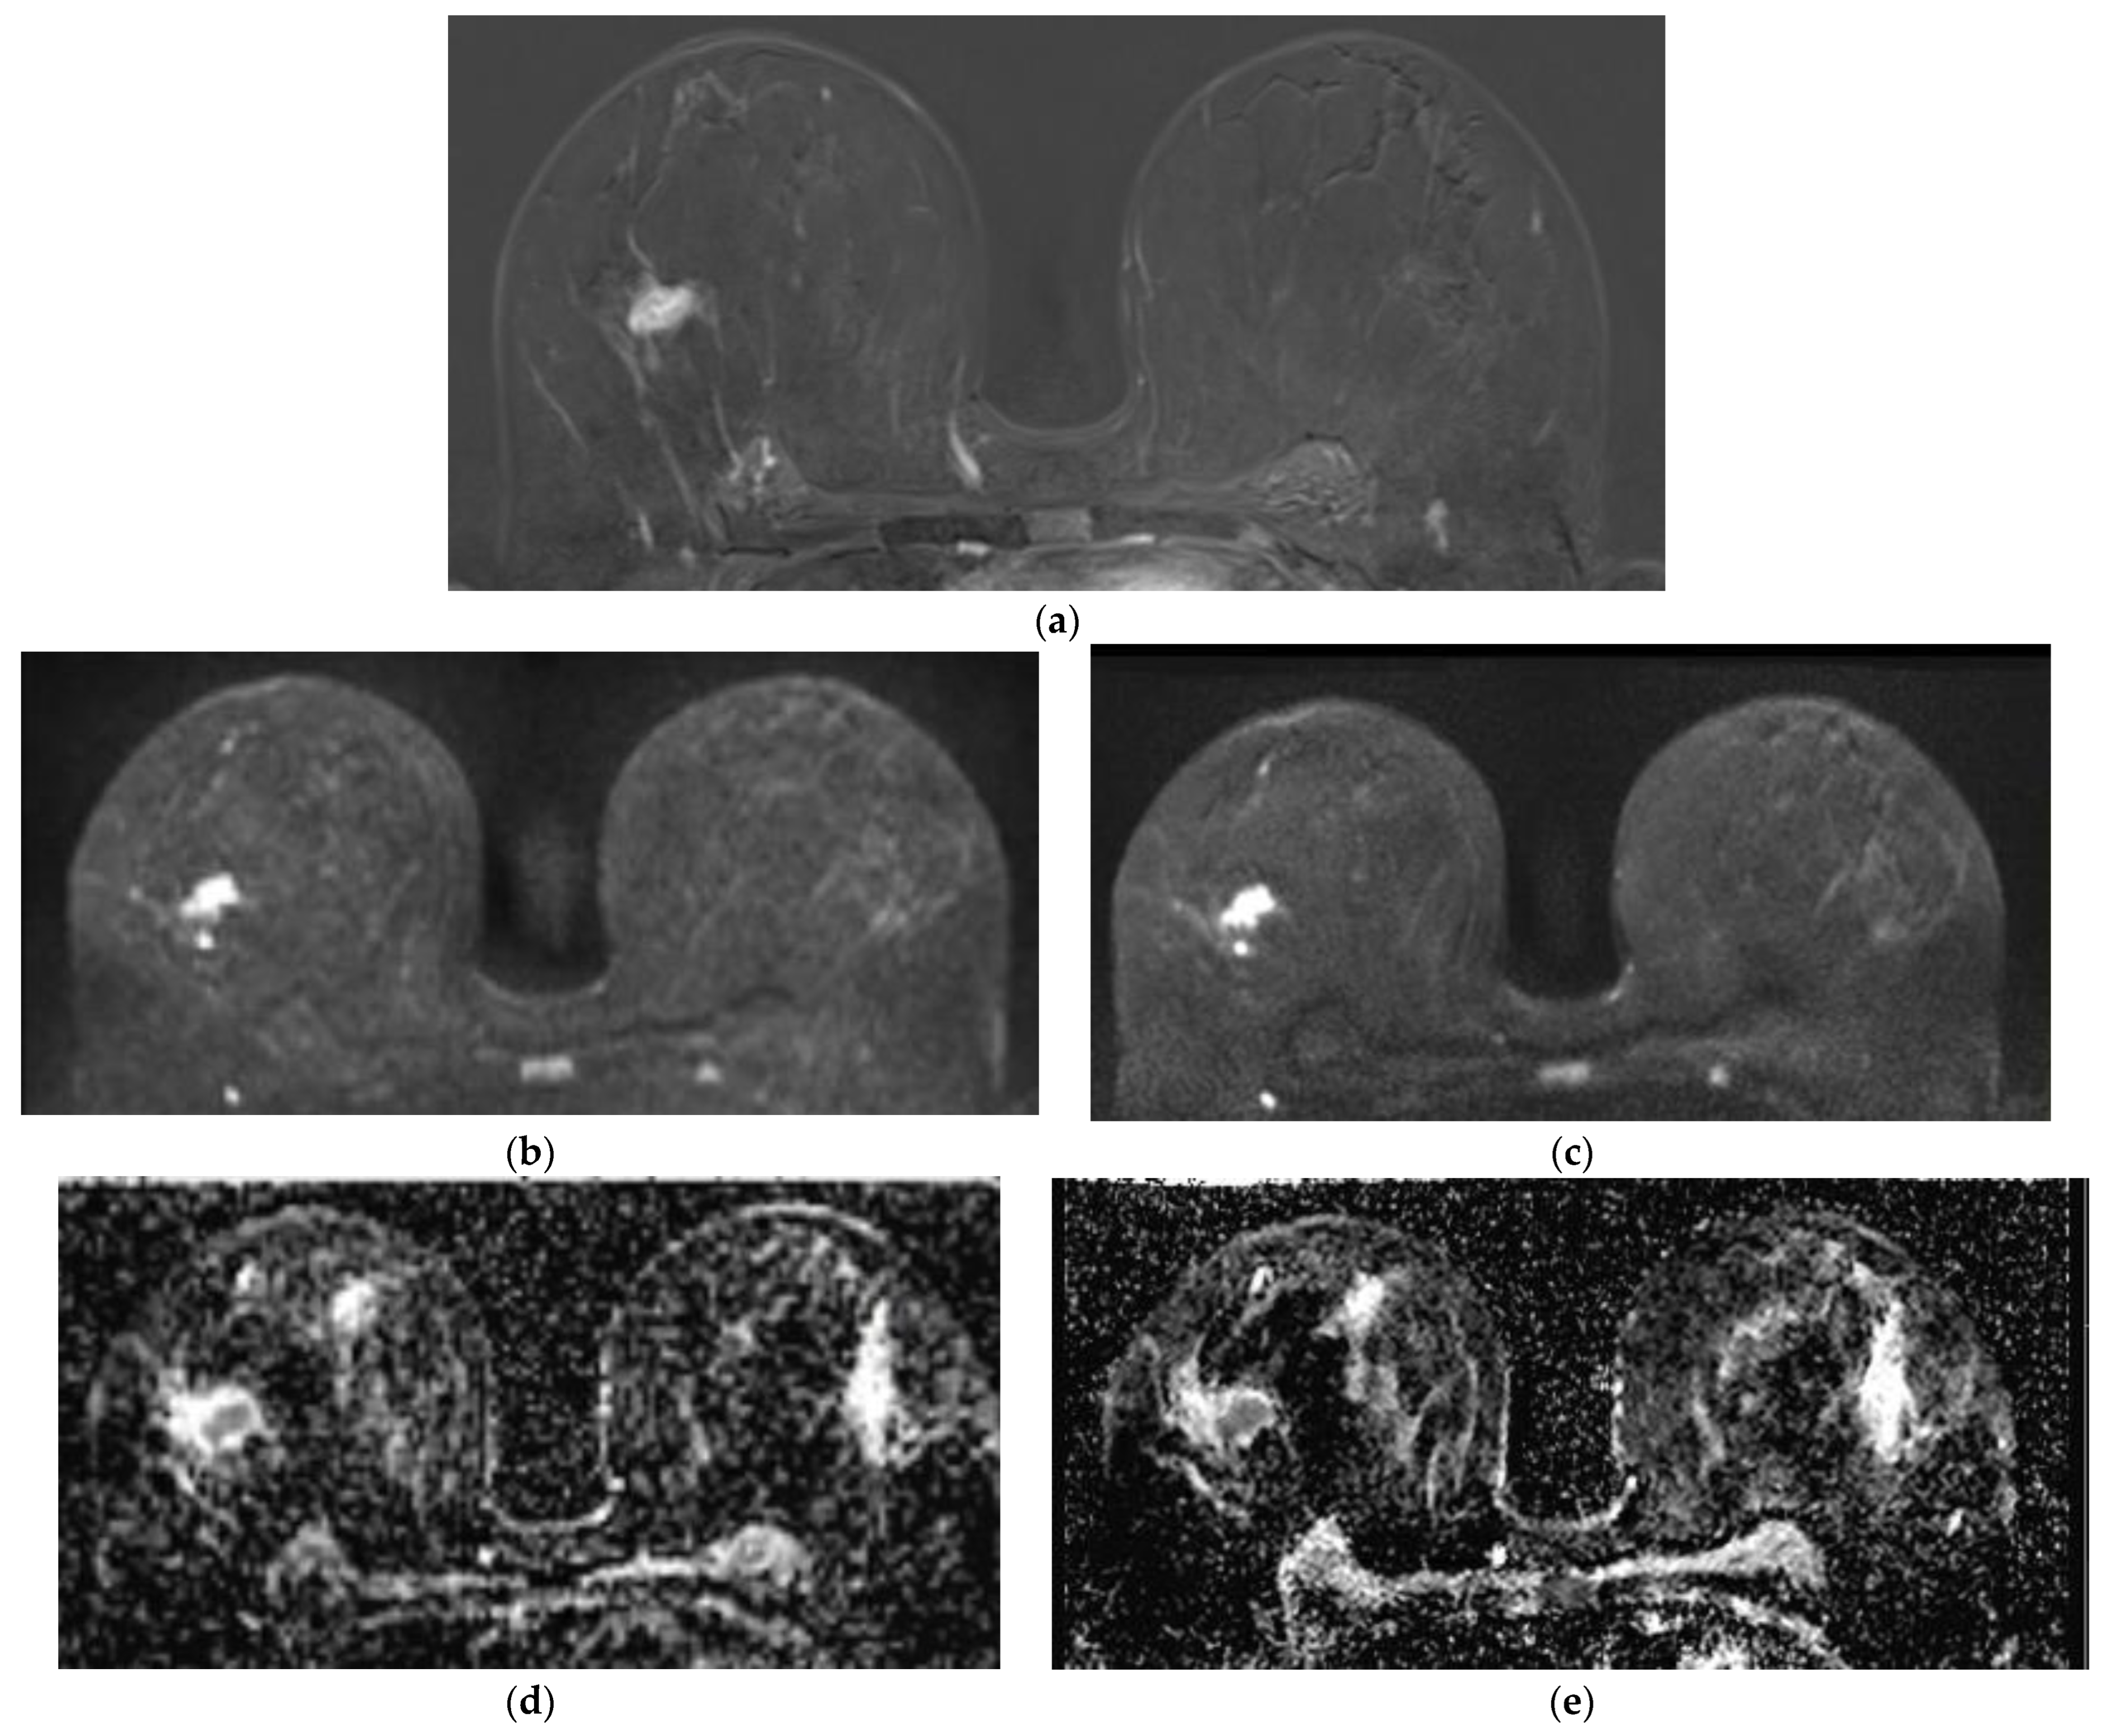

Qualitative Image Evaluation for DWI

Qualitative Image Evaluation for ADC